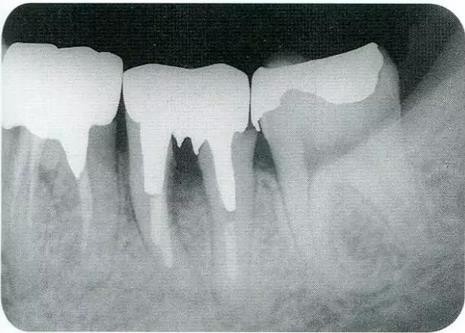

16-1 對右上6.7分叉部病變處理時,對包括右上4.5進行齦瓣分割,確認骨缺失狀態。右上7頰側存在著12mm的骨緣下缺失。

16-2 右上6水平的分叉部病變到達了III度。

在直視下對牙槽骨進行處理時,牙槽中間骨脊的垂直分類等級達到B或者C,通過Langer文獻表明對治療后長期性的恢復預測性較低。因此,根據情況的不同,也有必要考慮戰略性拔牙的診斷。